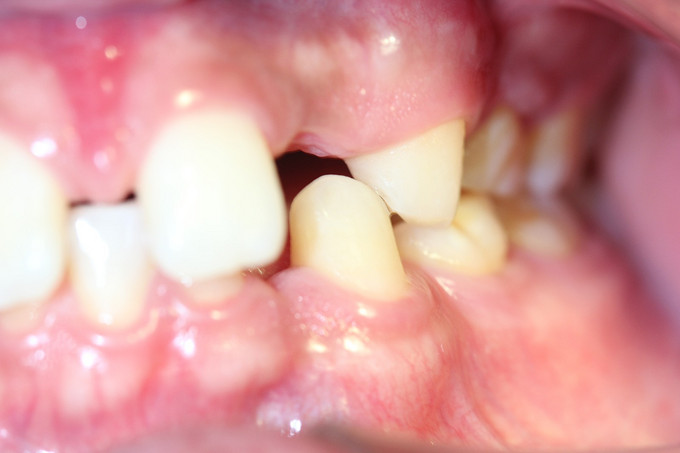

男 年龄16岁 右上恒牙2、3、4、5缺失,乳牙2、3、4、5滞留。 右下恒牙5缺失,乳牙5滞留。 左上恒牙2、3、4、5缺失,乳牙2、3、5滞留。 左下恒牙2、4、5缺失,乳牙2、5滞留。 诊断:恒牙先天缺失 治疗计划:a.乳牙治疗 b.唇系带手术 c.正畸治疗 d.种植体修复 现已经a、b两项治疗完成;因正畸难度较大,需要专家会诊共同完成!正畸治疗后再行种植修复。